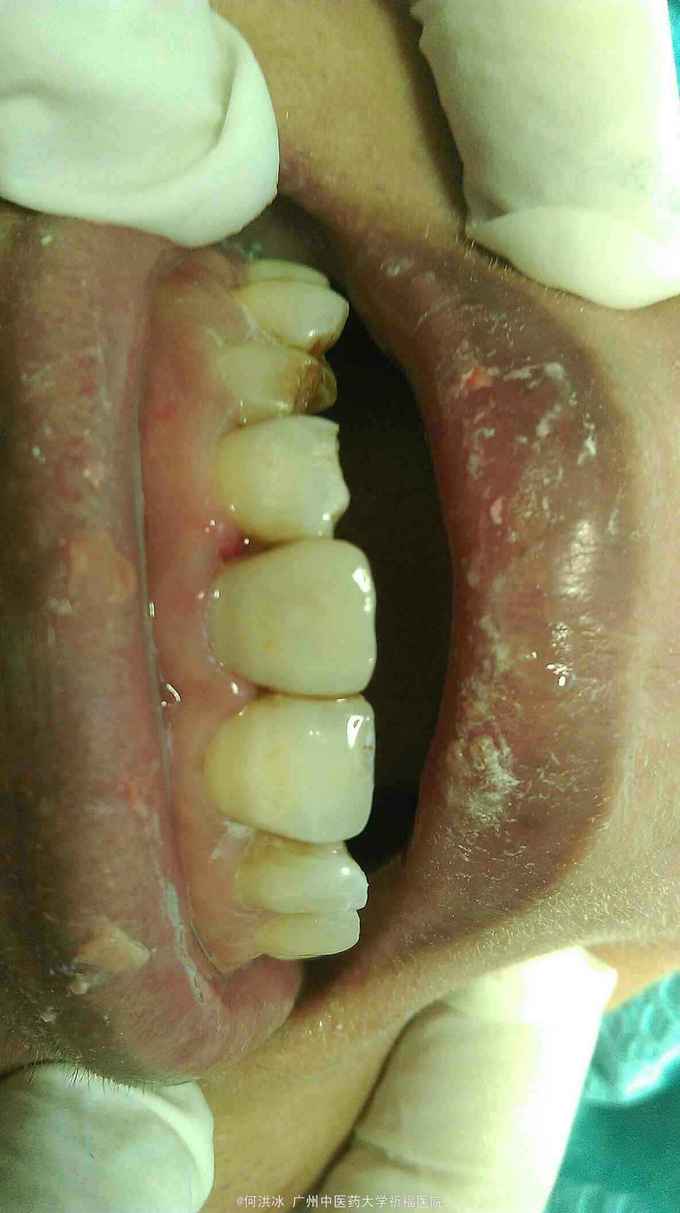

查体: 上下唇左侧有擦伤,痂皮已脱落。左侧口角处缝线已拆,触痛明显。牙齿检查,21-23牙冠折裂,其中21折断范围较大,远中切角缺如,最可喜的是,远中颊角及邻面处断面平龈,近远中邻接关系未破坏,牙髓暴露,叩痛明显。22,23切端折断,未露髓,暂无不适。 三牙牙体折断面已污染。 咬合关系检查,无明显高点,张口度可。 精神状态及依从性评估: 精神低落,极度敏感。一年前,家里发生变故,丈夫去世,一直睡眠质量较差。此次看牙,由新男友陪同,神情恍惚,不敢高声言语,但面部焦急不堪。经朋友介绍,来找我就医。说明病情,治疗、修复方案,知情同意。 辅查: 根尖片,21-23无根折,根尖区无阴影。

诊断: 21-23冠折,21急性牙髓炎 治疗修复方案: 21根管治疗,树脂修复。 步骤: 1,21局麻下拔髓,调咬合,初步急性处理。折断面暂不做任何处理。转治疗医生。 2,分层树脂修复21。 A,清洗断面,打磨锐利边缘,无基釉,砂纸、毛刷抛光粘结面。 B,比色。 C,隔湿,排龈,成型片隔离邻牙。 D,酸蚀,涂粘结剂。 E,分层树脂充填。硅橡胶舌侧树脂薄翼,简化操作难度,节省材料。 F,修形,抛光,涂偶联剂。 3,延期树脂修复22,23。